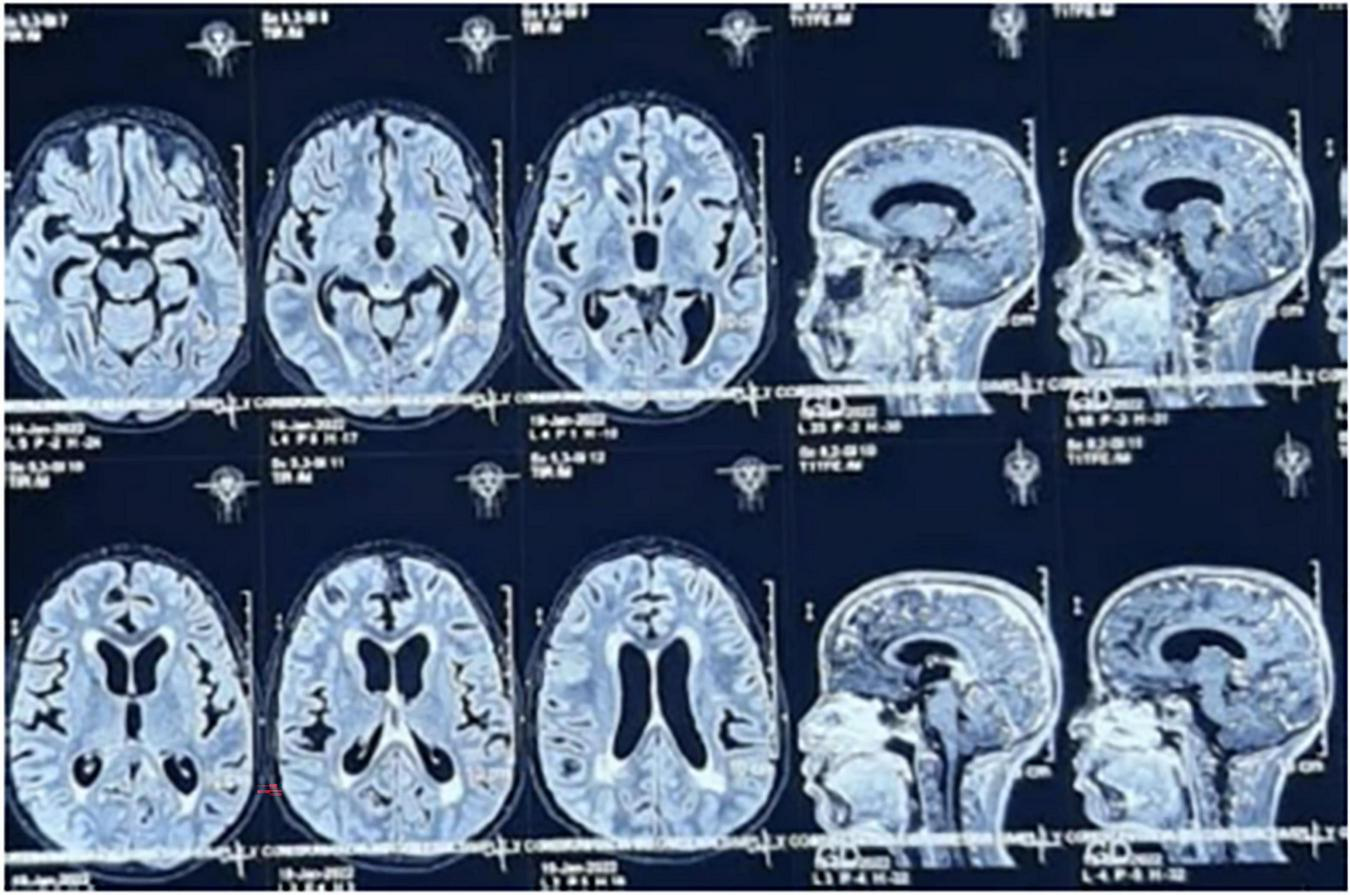

In the following weeks at home, his clinical condition deteriorated, with anxiety episodes, worsening and altered seizure patterns, recurrent fever, more intense holocranial headaches, and photophobia. He was readmitted for hospitalization; brain magnetic resonance imaging (MRI) during this admission revealed ventricular dilation and patchy hyperintensities in the periventricular white matter, without signs of cerebrospinal fluid flow obstruction findings consistent with intracranial hypertension (Figure 2).

FIGURE 2

MRI without contrast shows evidence on T2-weighted sequences of abnormal contrast enhancement of the cerebral and cerebellar leptomeninges, cortical and central cerebral atrophy, and ventricular system dilation.